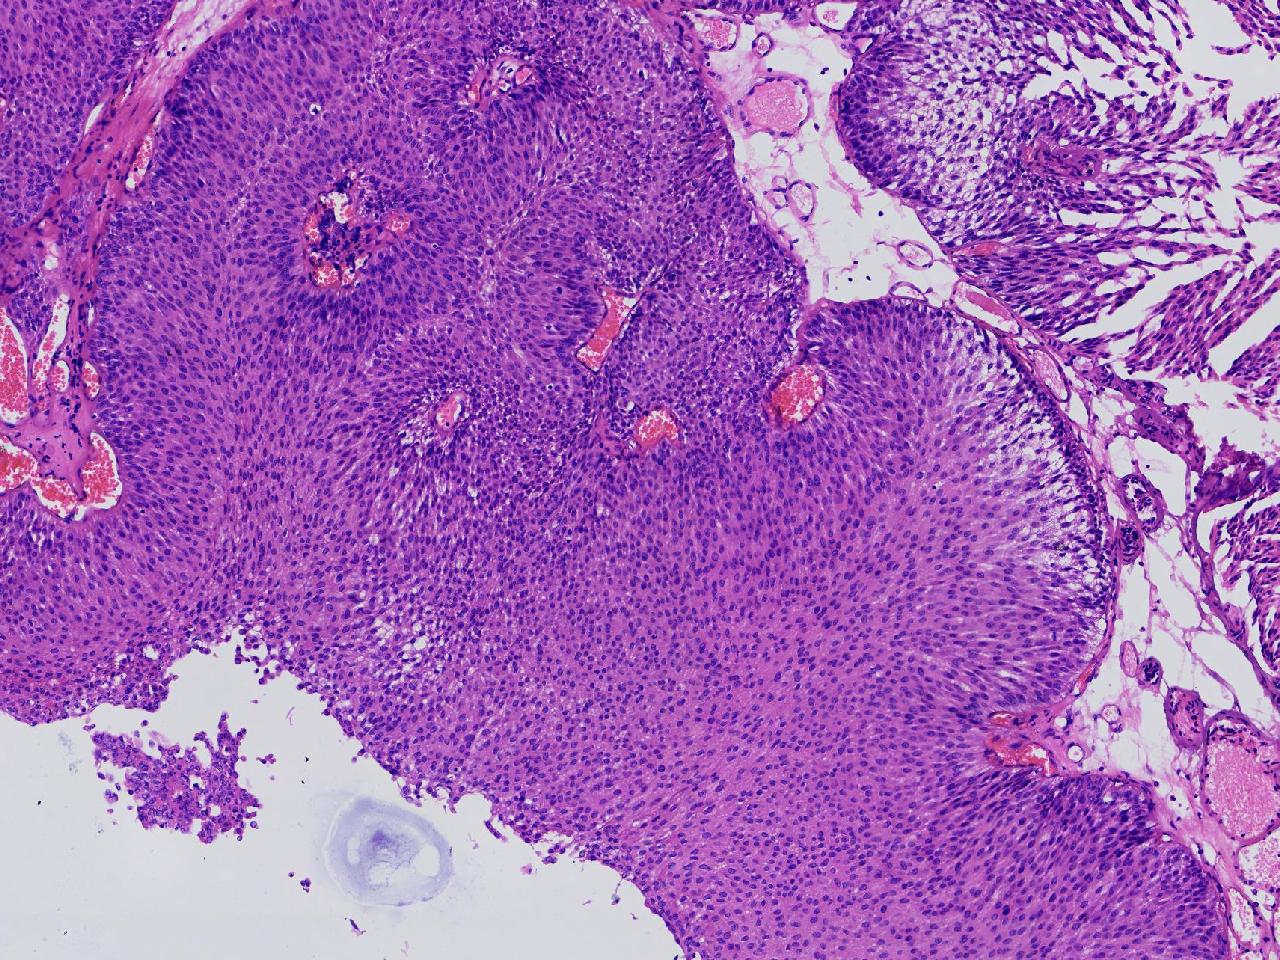

男,79岁,膀胱肿物。

膀胱肿物

灰白色不整形软组织多块,2X1X1厘米。

考虑:乳头状尿路上皮癌

考虑低级别,非浸润。

乳头状尿路上皮癌,低级别。

这几张图片上没有看到明确的浸润。